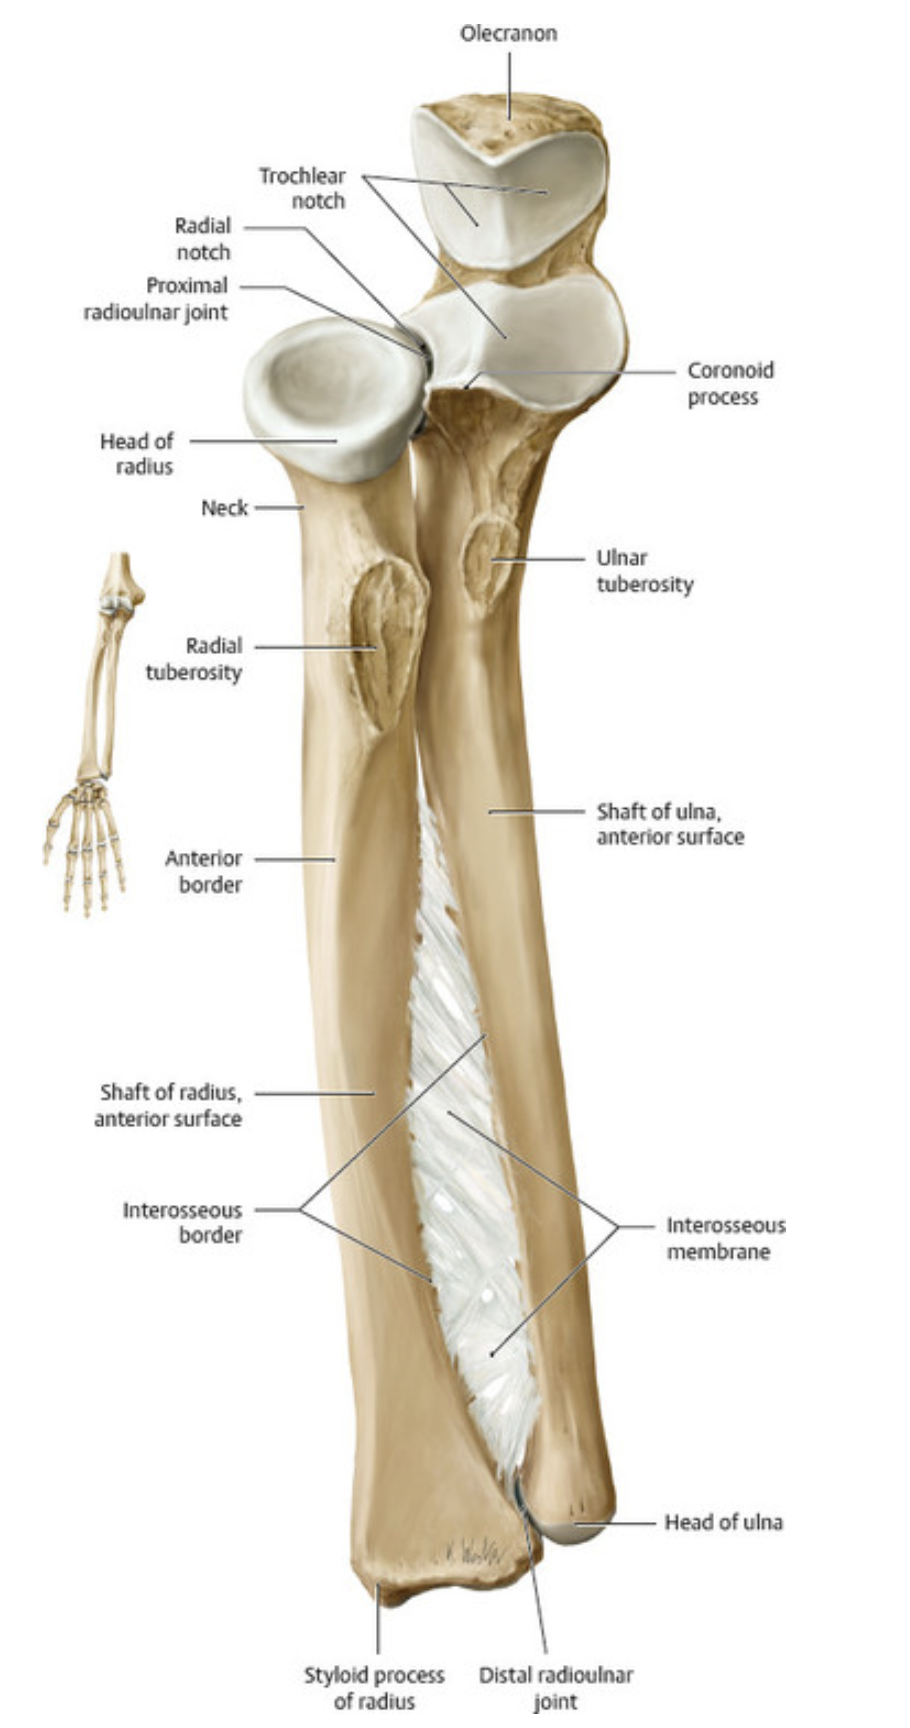

The head of the humerus articulates with the ___ at the ___ joint. The __ and ___ of the humerus articulate with the radius and ulna, respectively, at the elbow (cubital) joint.

The head of the humerus articulates with the scapula at the glenohumeral joint. The capitulum and trochlea of the humerus articulate with the radius and ulna, respectively, at the elbow (cubital) joint.

Anterior view. The acromioclavicular joint is a ___ joint. Because the articulating surfaces are flat, they must be held in place by strong ligaments, greatly limiting the mobility of the joint.

Anterior view. The acromioclavicular joint is a plane joint. Because the articulating surfaces are flat, they must be held in place by strong ligaments, greatly limiting the mobility of the joint.